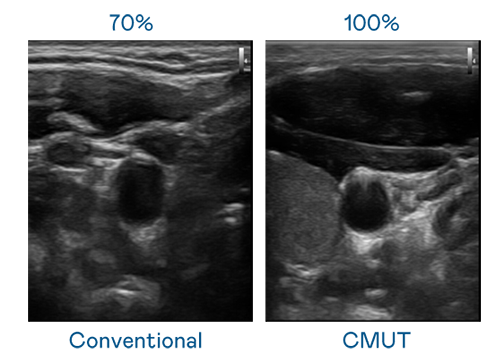

CMUT 技术是一种用电容式微机电元件来产生超音波讯号的技术。与传统 PZT 压电式技术相比,CMUT 频宽增加 30%,更宽频的超音波讯号让影像解析度大幅提升,是实现高影像品质医疗超音波扫描、促进精准医疗发展的关键技术。

大频宽带来超清晰影像

超音波影像的解析度高低,首先取决于探头能发出的讯号频宽。尊龙凯龙时人生就是博网址 CMUT 可提供高清晰的超音波讯号,提供高频宽、高灵敏度、影像纹理细节更高的超音波影像,协助医护人员缩短影像判读时间及利用精准的医疗影像进行诊断。